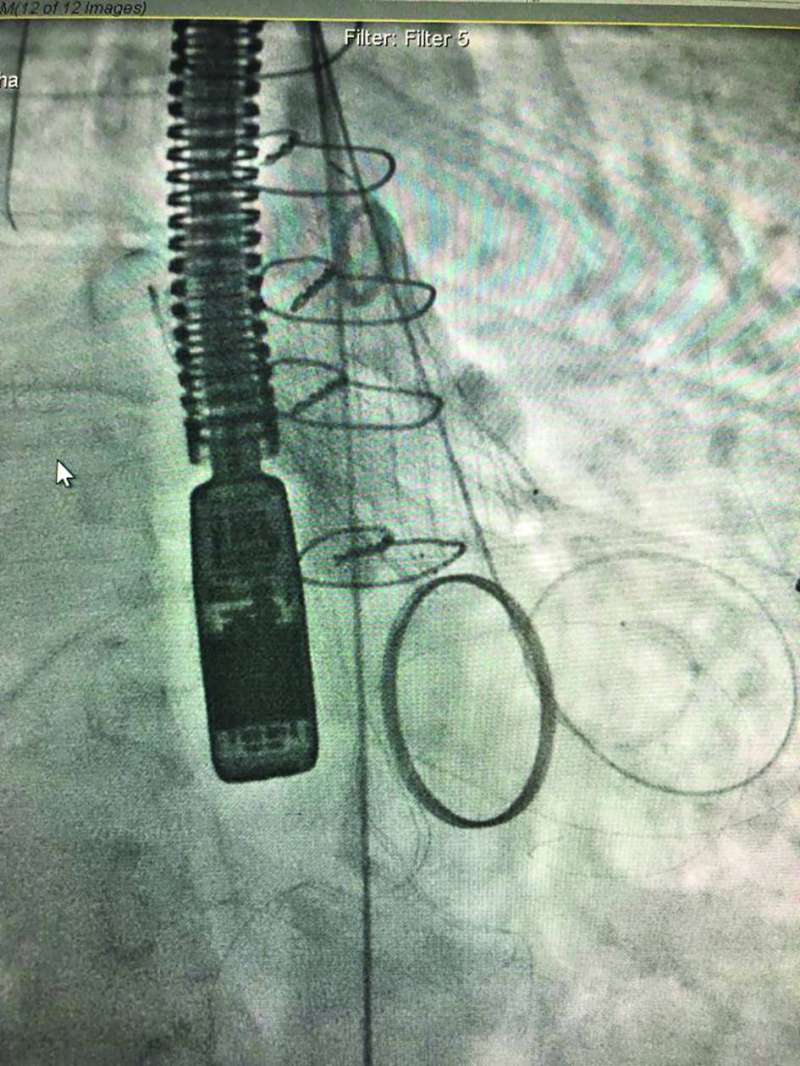

فقد استطاع الفريق تبديل صمام أورطي عن طريق القسطره (TAVI) باستخدام الصمام الحديث (EvolutFX) لمريضة في العقد السابع من عمرها، بعد إصابتها بضيق شديد بالصمام، مما أدى إلى دخولها إلى المستشفى بارتشاح رئوي.

وقال الدكتور العسعوسي لـ «الراي»، إن «المريضة كانت قد خضعت لعملية تبديل صمام ميترالي معدني في عملية قلب مفتوح منذ عشر سنوات، فيما كانت المسافة بين الصمام المعدني ومكان وضع الصمام الأورطي الجديد لا تتجاوز 2 مليمتر، وهى أقل مسافة ذُكرت في التقارير الطبية العالمية فى مثل هذه الحالات النادرة».

وأضاف «ساعدت التقنية الجديدة في الصمام، بوجود طبقة تساعد على ثباته بوضعه المحدد بدقة في هذه المسافة الضئيلة،على نجاح عمل تبديل الصمام. وقد تمت الاستعانه بسونار القلب عن طريق المريء وتقنية الإيكو ثلاثي الأبعاد (3D TOE) لتثبيت ووضع الصمام بدقة شديدة من دون التداخل مع شرفات الصمام الميترالي المعدني. وتعد هذه الحالة الأولى من نوعها في الشرق الأوسط، من الحالات النادرة عالمياً، التي يتم فيها تبديل الصمام الأورطي عن طريق القسطرة بوجود صمام ميترالي معدني باستخدام مثل هذه التقنيات الحديثة».

من جانبه، قال الدكتور طه لـ «الراي»، إنه «في حالة ثانية ساعدت نفس التقنية الحديثة باستخدام الصمام الجديد في تبديل صمام اورطي، ووضعه بدقة شديدة لمريض في العقد الثامن بوجود شريان أورطي مستعرض (Horizontal Aorta) بزواية إنزال تصل إلى 80 درجة، مما يسبب صعوبة شديدة في وضع الصمام بدقة في مثل هذه الحالات النادرة».